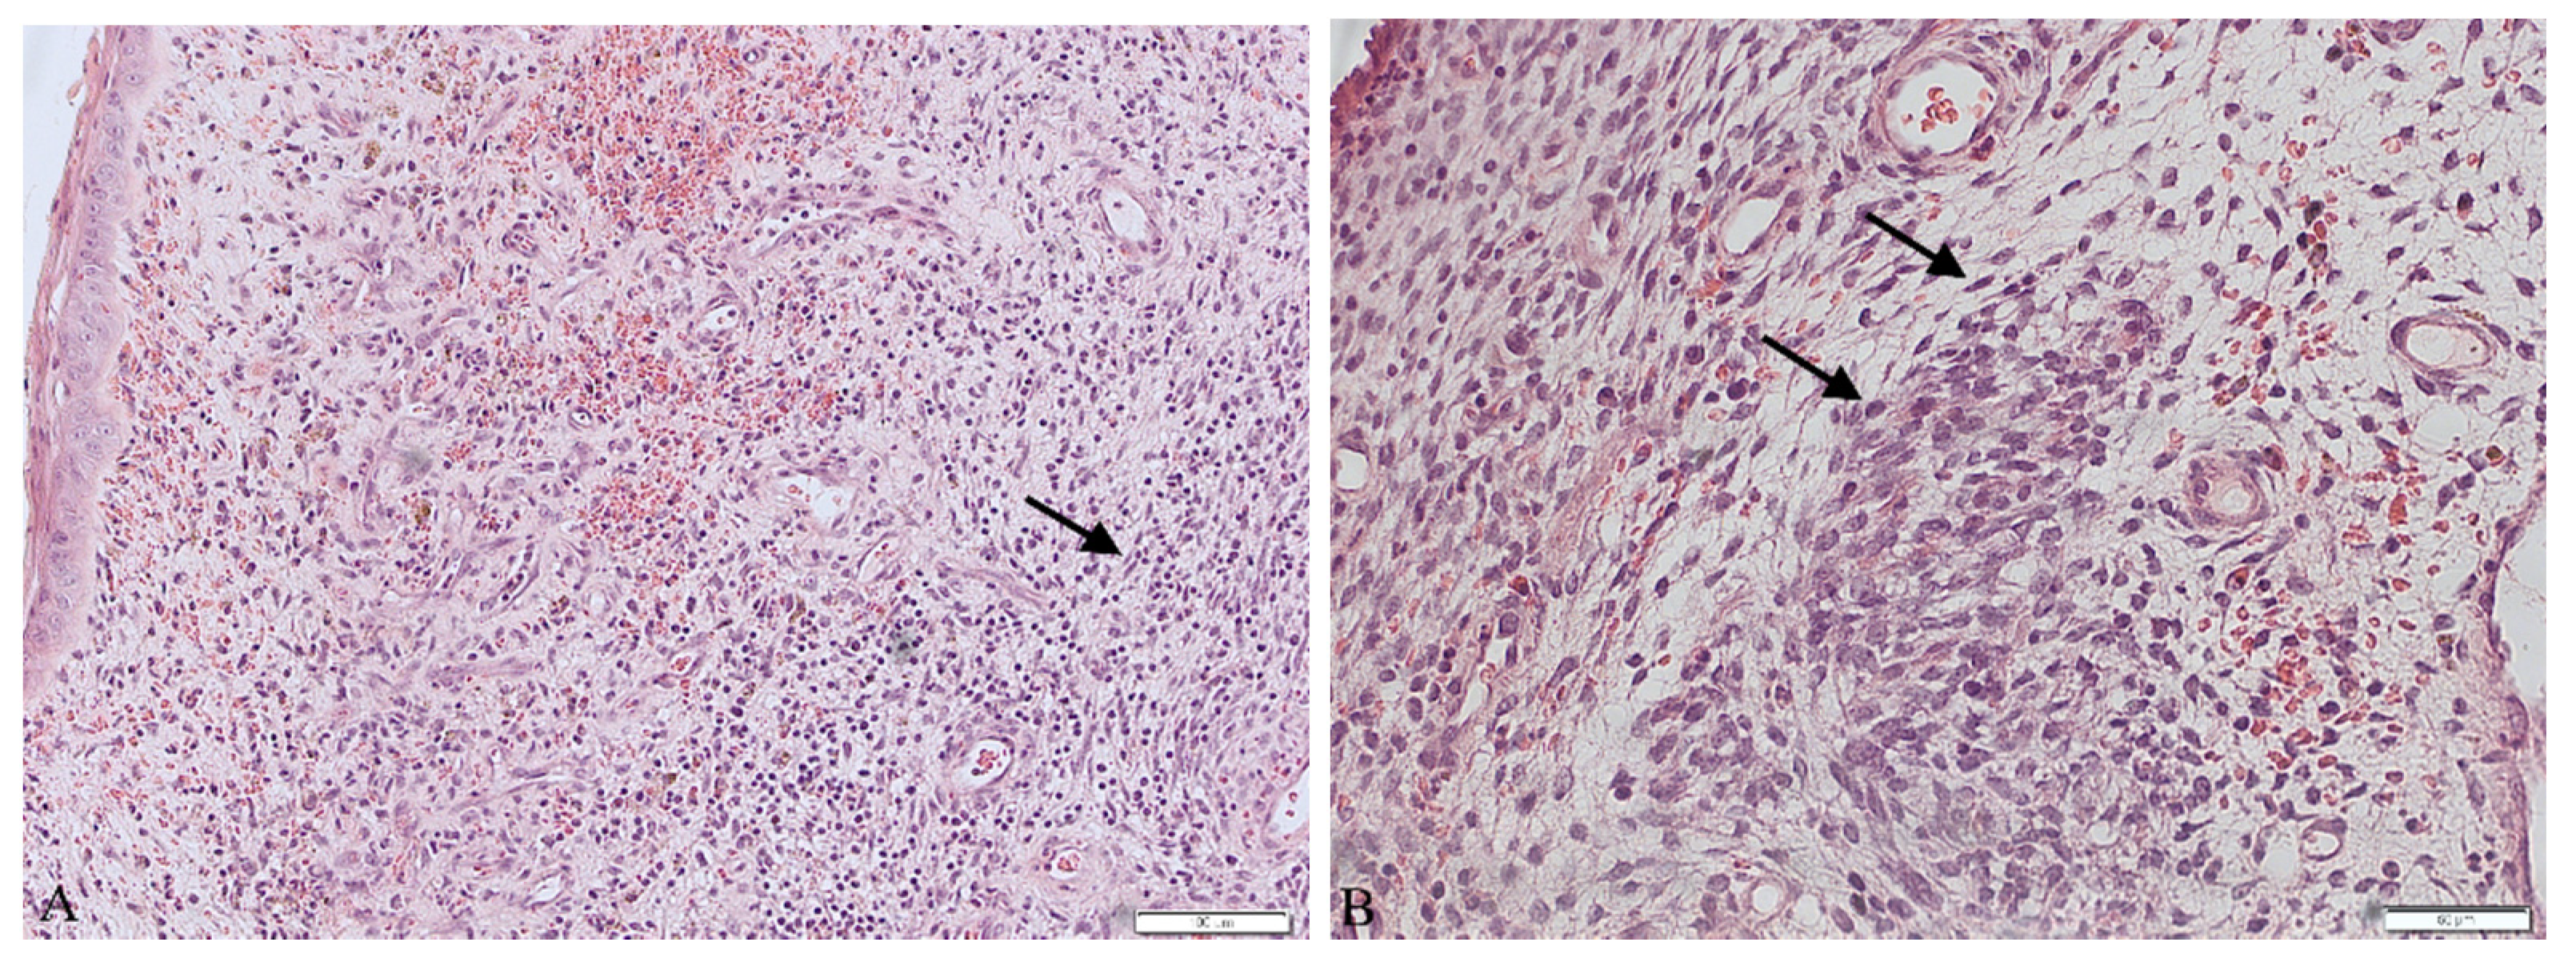

The patient underwent a surgical procedure of excising the polyp at its peduncle using a LEEP loop electrode. It could not be removed in one piece—the polyp fragmented into several pieces during extraction. Then, a curettage of the cervix and an unsuccessful attempt of a uterine cavity curettage was performed. Obtained tissues were then sent to the pathology department for a histopathological examination. The findings were ready in six weeks after the procedure and revealed the presence of rhabdomyosarcoma embryonale (type botryoides) in the excised polyp. Due to the fact that the polyp was fragmented during extraction, a precise margin status or the depth of invasion could not be properly determined. Histopathological images are presented in Figure 1.

Post-menopausal hemorrhaging is, on the other hand, a common symptom, affecting almost 1 in 10 women worldwide. Out of all these cases, 10% are caused by neoplasms [14]. As other studies show, vaginal bleeding is also the most common symptom in RMS of the genitourinary tract. Other symptoms include abdominal and lower pelvic pain or frequent urination [9]. When dealing with patients complaining about abnormal vaginal bleeding, a careful approach is advised. Performing a histopathological examination of the tissues collected from uterine curettage is necessary, because it can allow us to diagnose even such uncommon problems as ERMS. Histopathological evaluation of the excised material is often a complicated task when dealing with sarcomas. The reason for that is the fact that sarcomas present a very diverse image. Embryonal rhabdomyosarcoma usually presents a few traits: agglomerations of spindle and round pleomorphic cells with hyperchromatic nuclei, rhabdomyoblasts and myxoid stroma [9,10,11]. Performing an immunohistochemical profile of the tissue is nowadays a must in diagnosing sarcomas. In the case of rhabdomyosarcoma, staining for myoglobin, desmin and muscle-specific actin is observed. The most sensitive and specific RMS markers are myogenin and Myo-D1, proteins characteristic for early differentiation of muscle cells, and they often prove to be the key traits in making the final diagnosis [15,16]. In our case, the immunohistochemistry showed positive CD10, myogenin and desmin and negative SMA, ER, PR and S100 markers. These results, combined with microscopic description, allowed us to perform differential diagnosis and rule out more common out neoplasms occurring more frequently, such as the leiomyosarcoma or adeno-sarcoma, as well as identify a specific subtype of RMS—rhabdomyosarcoma embryonale botryoides in this case.

Figure 1. Histopathological images of the excised polyp (A) in 10× magnification. (B) in 20× magnification. Arrows show spindle and round pleomorphic cells with hyperchromatic nuclei and scant cytoplasm.